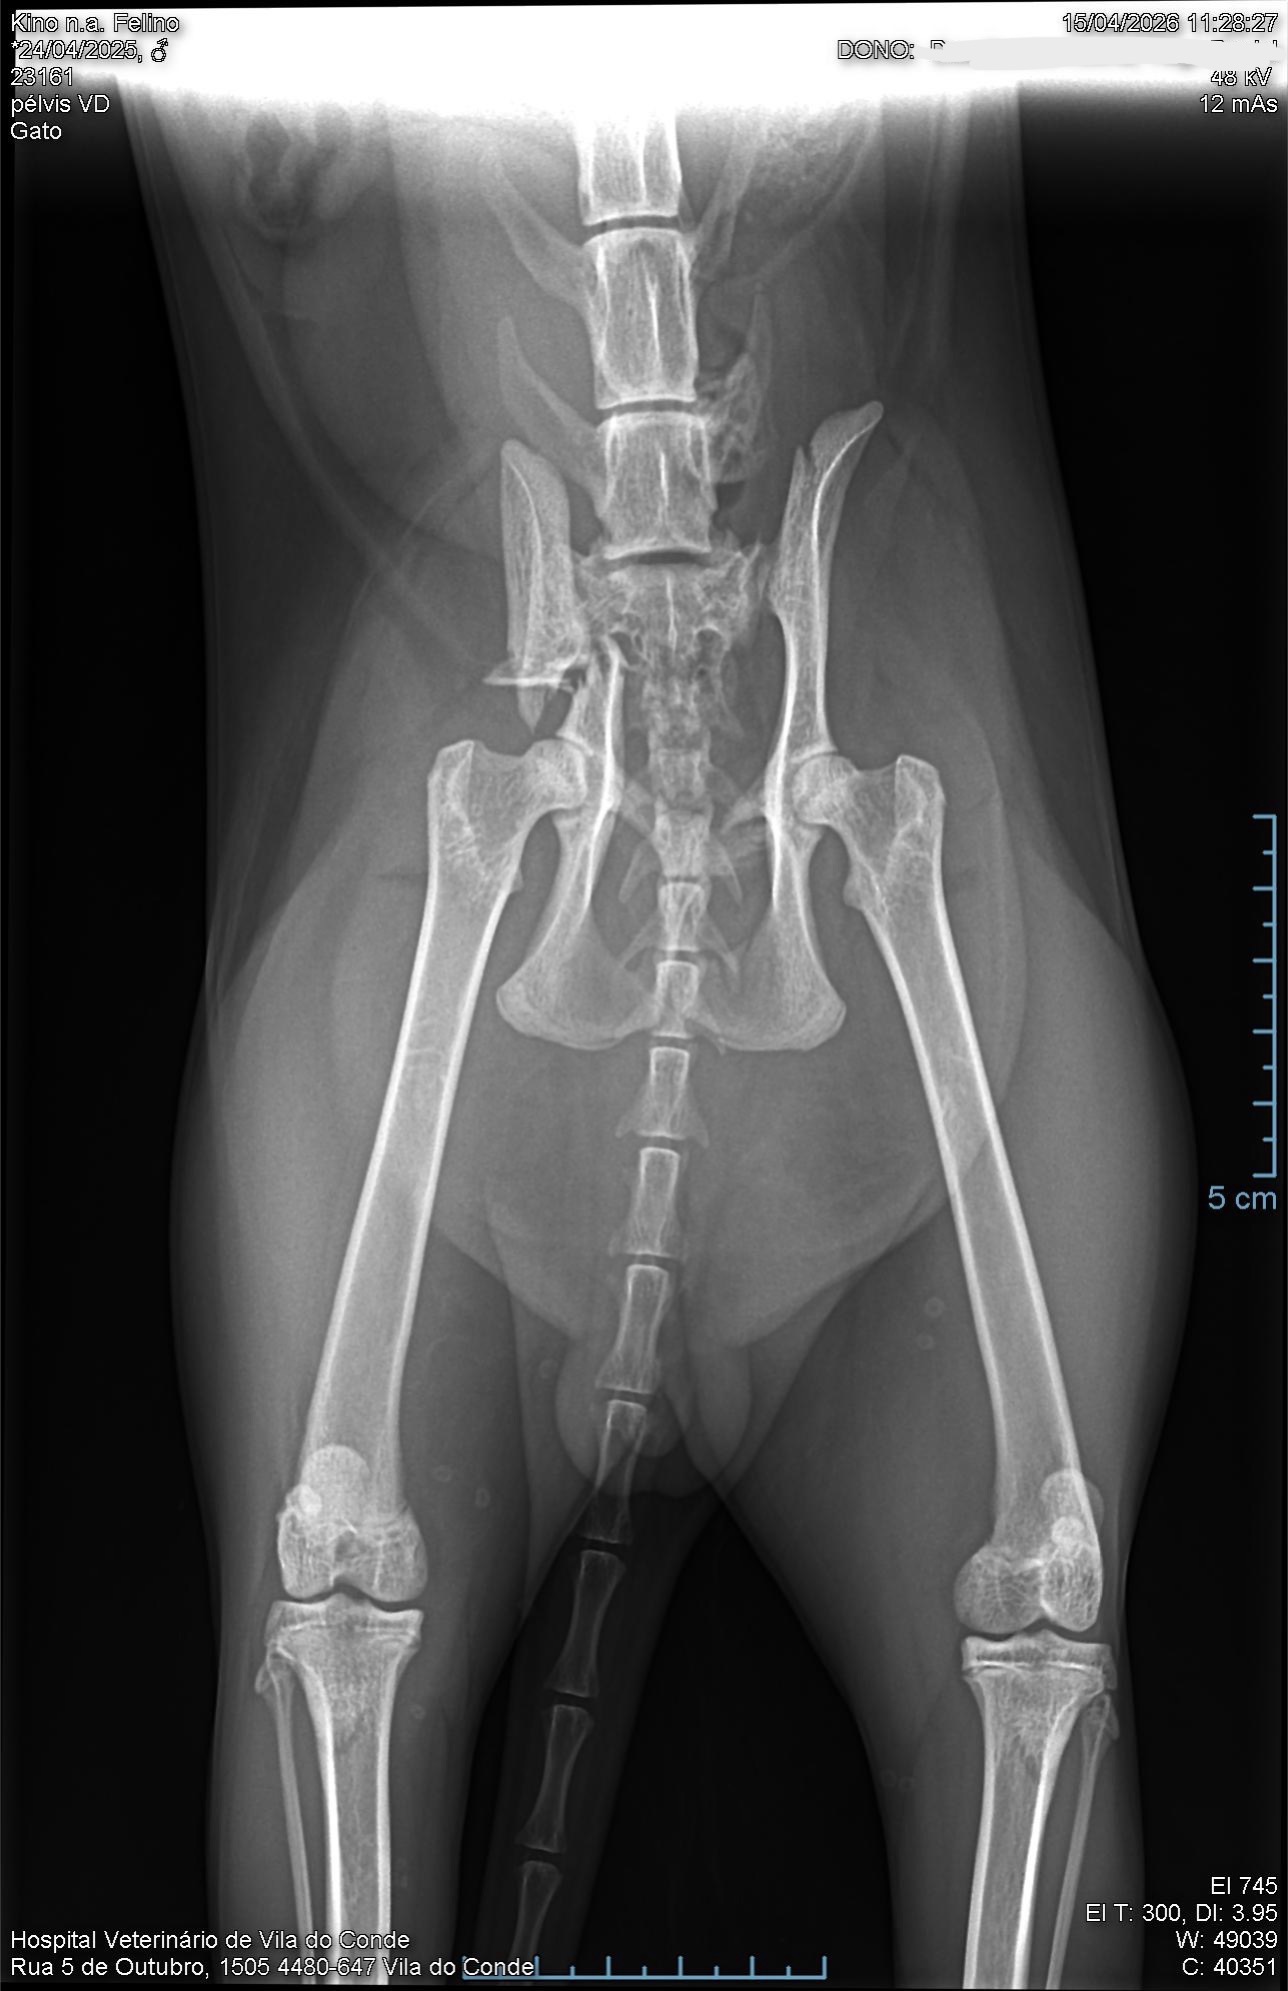

Hi everyone. You probably came from my post on r/cats. This is a fundraiser for Kino, my 1 year old cat who was hit by a car on 15/04 and will go through surgery on his hip. I shared a story of how our lives crossed paths, since being raised by his stray mom and how I helped her and the kittens.

There is also an alternative view of the x-ray.